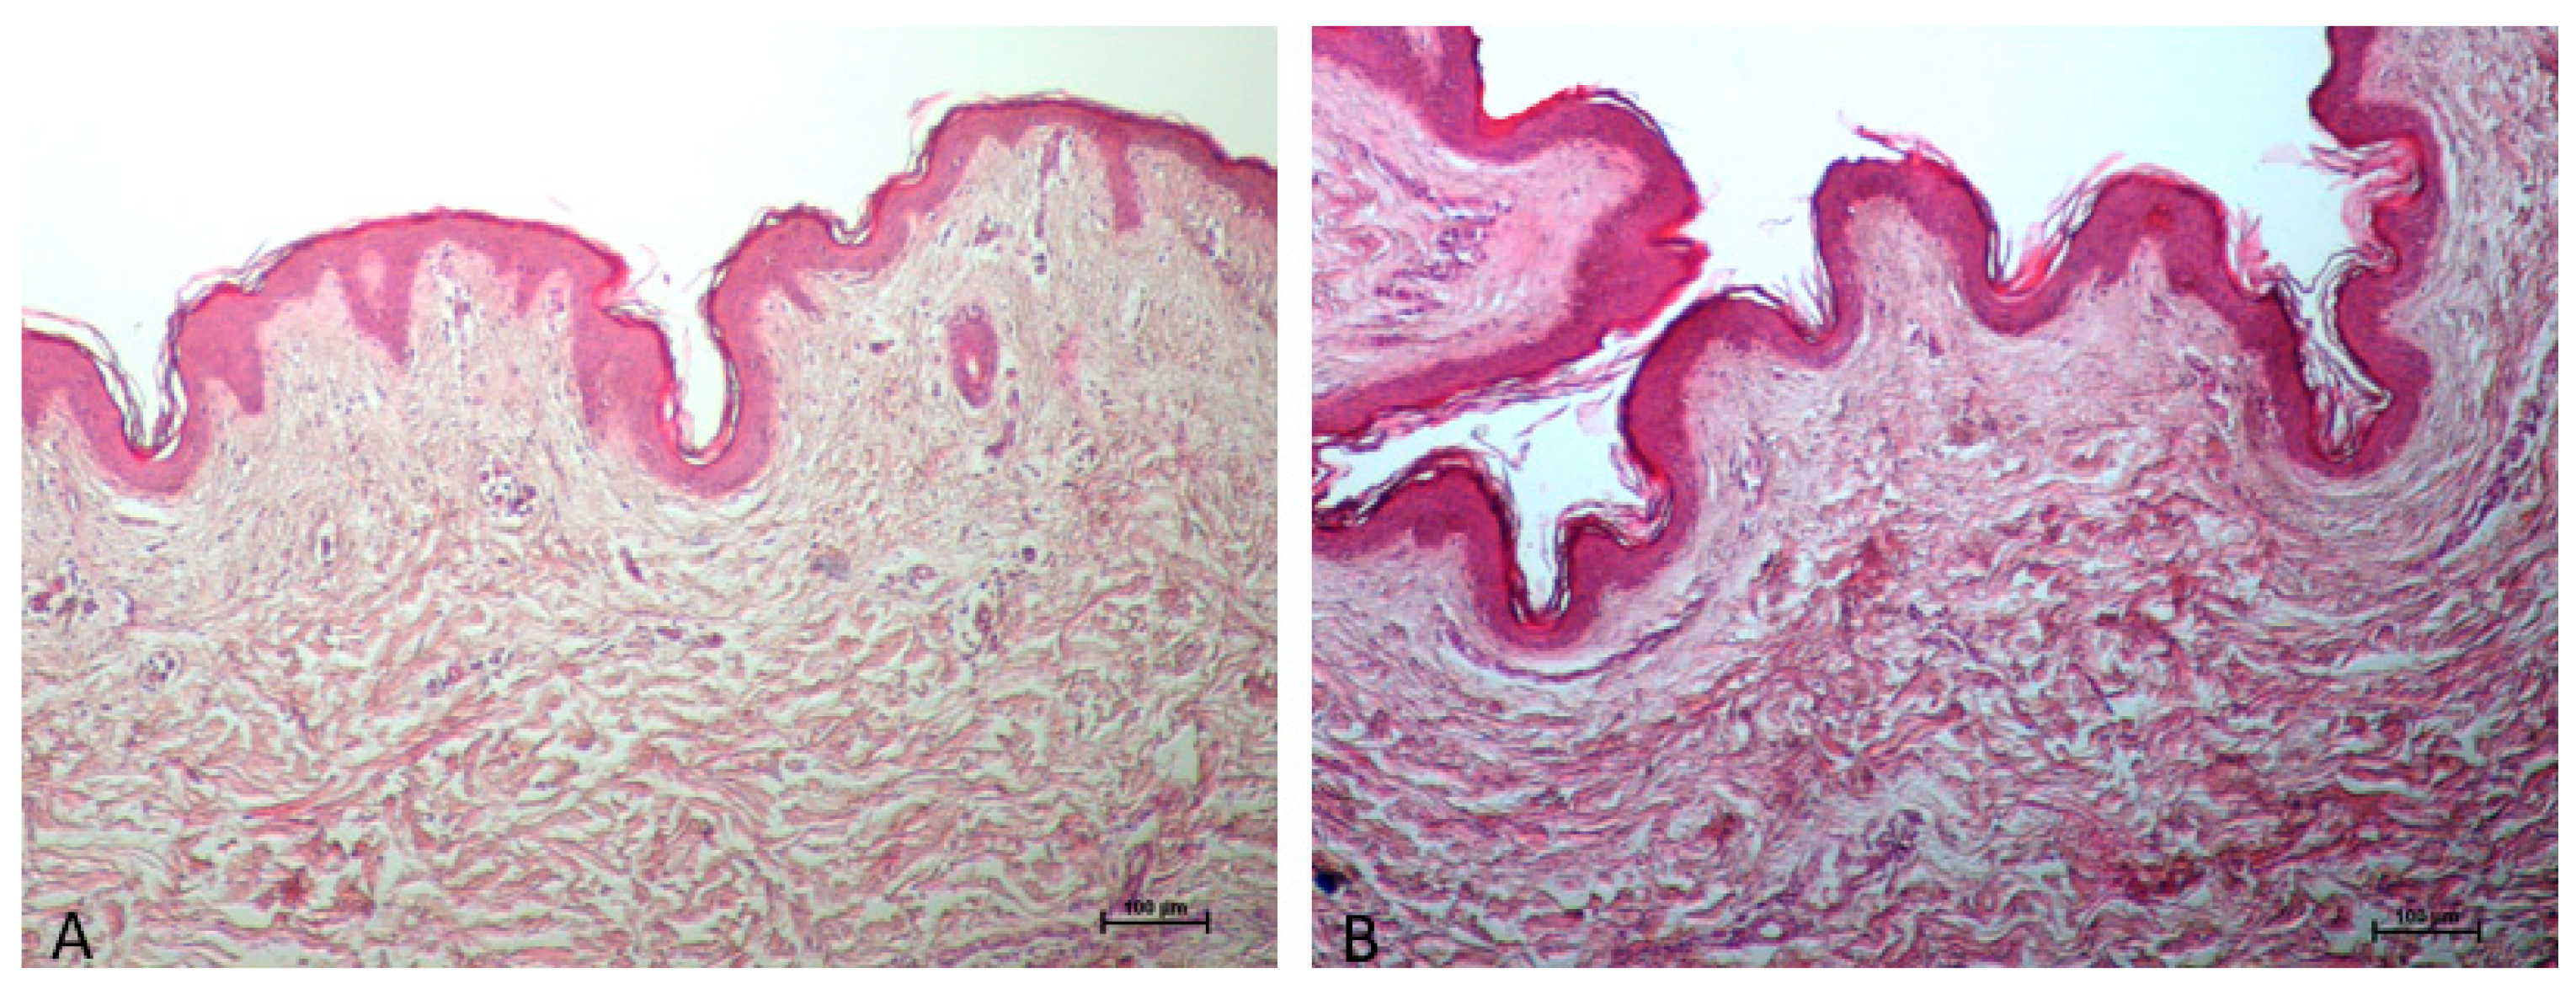

Histological analysis: Thanks to the skin cooling caused by the device handpiece, there are no differences in the epidermis and derma between the control (Figure 1A) and treated samples (Figure 1B).

Figure 1.

The treated sample’s epidermis (B) does not differ from the control sample (A) in any way; no changes can be noticed in epidermis immediately after treatment (B) because of skin cooling performed by the device handpiece. Additionally, the dermis’s collagen seems to be strongly colored as a result of the heat-induced shrinkage or tightening of the collagen, which increases eosinophilia. ((A,B) 10× Magnifications).